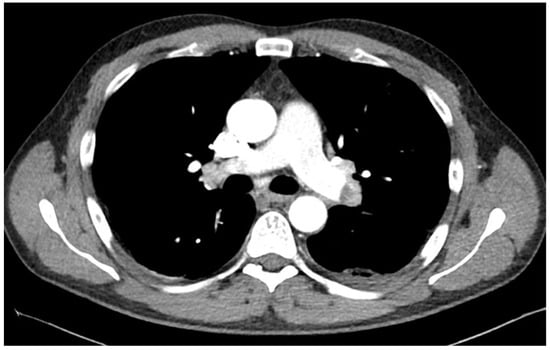

2. Case